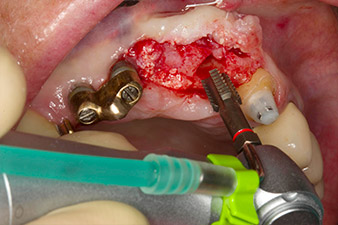

Per compensare la perdita ossea periodontale e ottenere un risultato estetico piacevole, si è proceduto all'impianto unitamente alla rigenerazione guidata dell'osso (tecnica GBR) con materiale di riempimento xenogenico e membrana di collagene (Fig. 5 e 6).

Materiale xenogenico di sostituzione ossea

Fig. 5: Al fine di ottenere la migliore qualità possibile del tessuto periimpianto, è stato eseguito innesto osseo nella sede di impianto con materiale xenogenico di sostituzione ossea e una membrana di collagene, in vista della rigenerazione guidata dell'osso.

Situazione in seguito a impianto

Fig. 6: Situazione in seguito a impianto e innesto: Il ponte vecchio è stato reinserito come ricostruzione temporanea durante la fase di guarigione con una protesi fresata in corrispondenza della posizione di impianto 22. La protesi finale programmata sarà un ponte in ossido di zirconio da 12 nell'impianto di inserimento in corrispondenza della posizione 23.